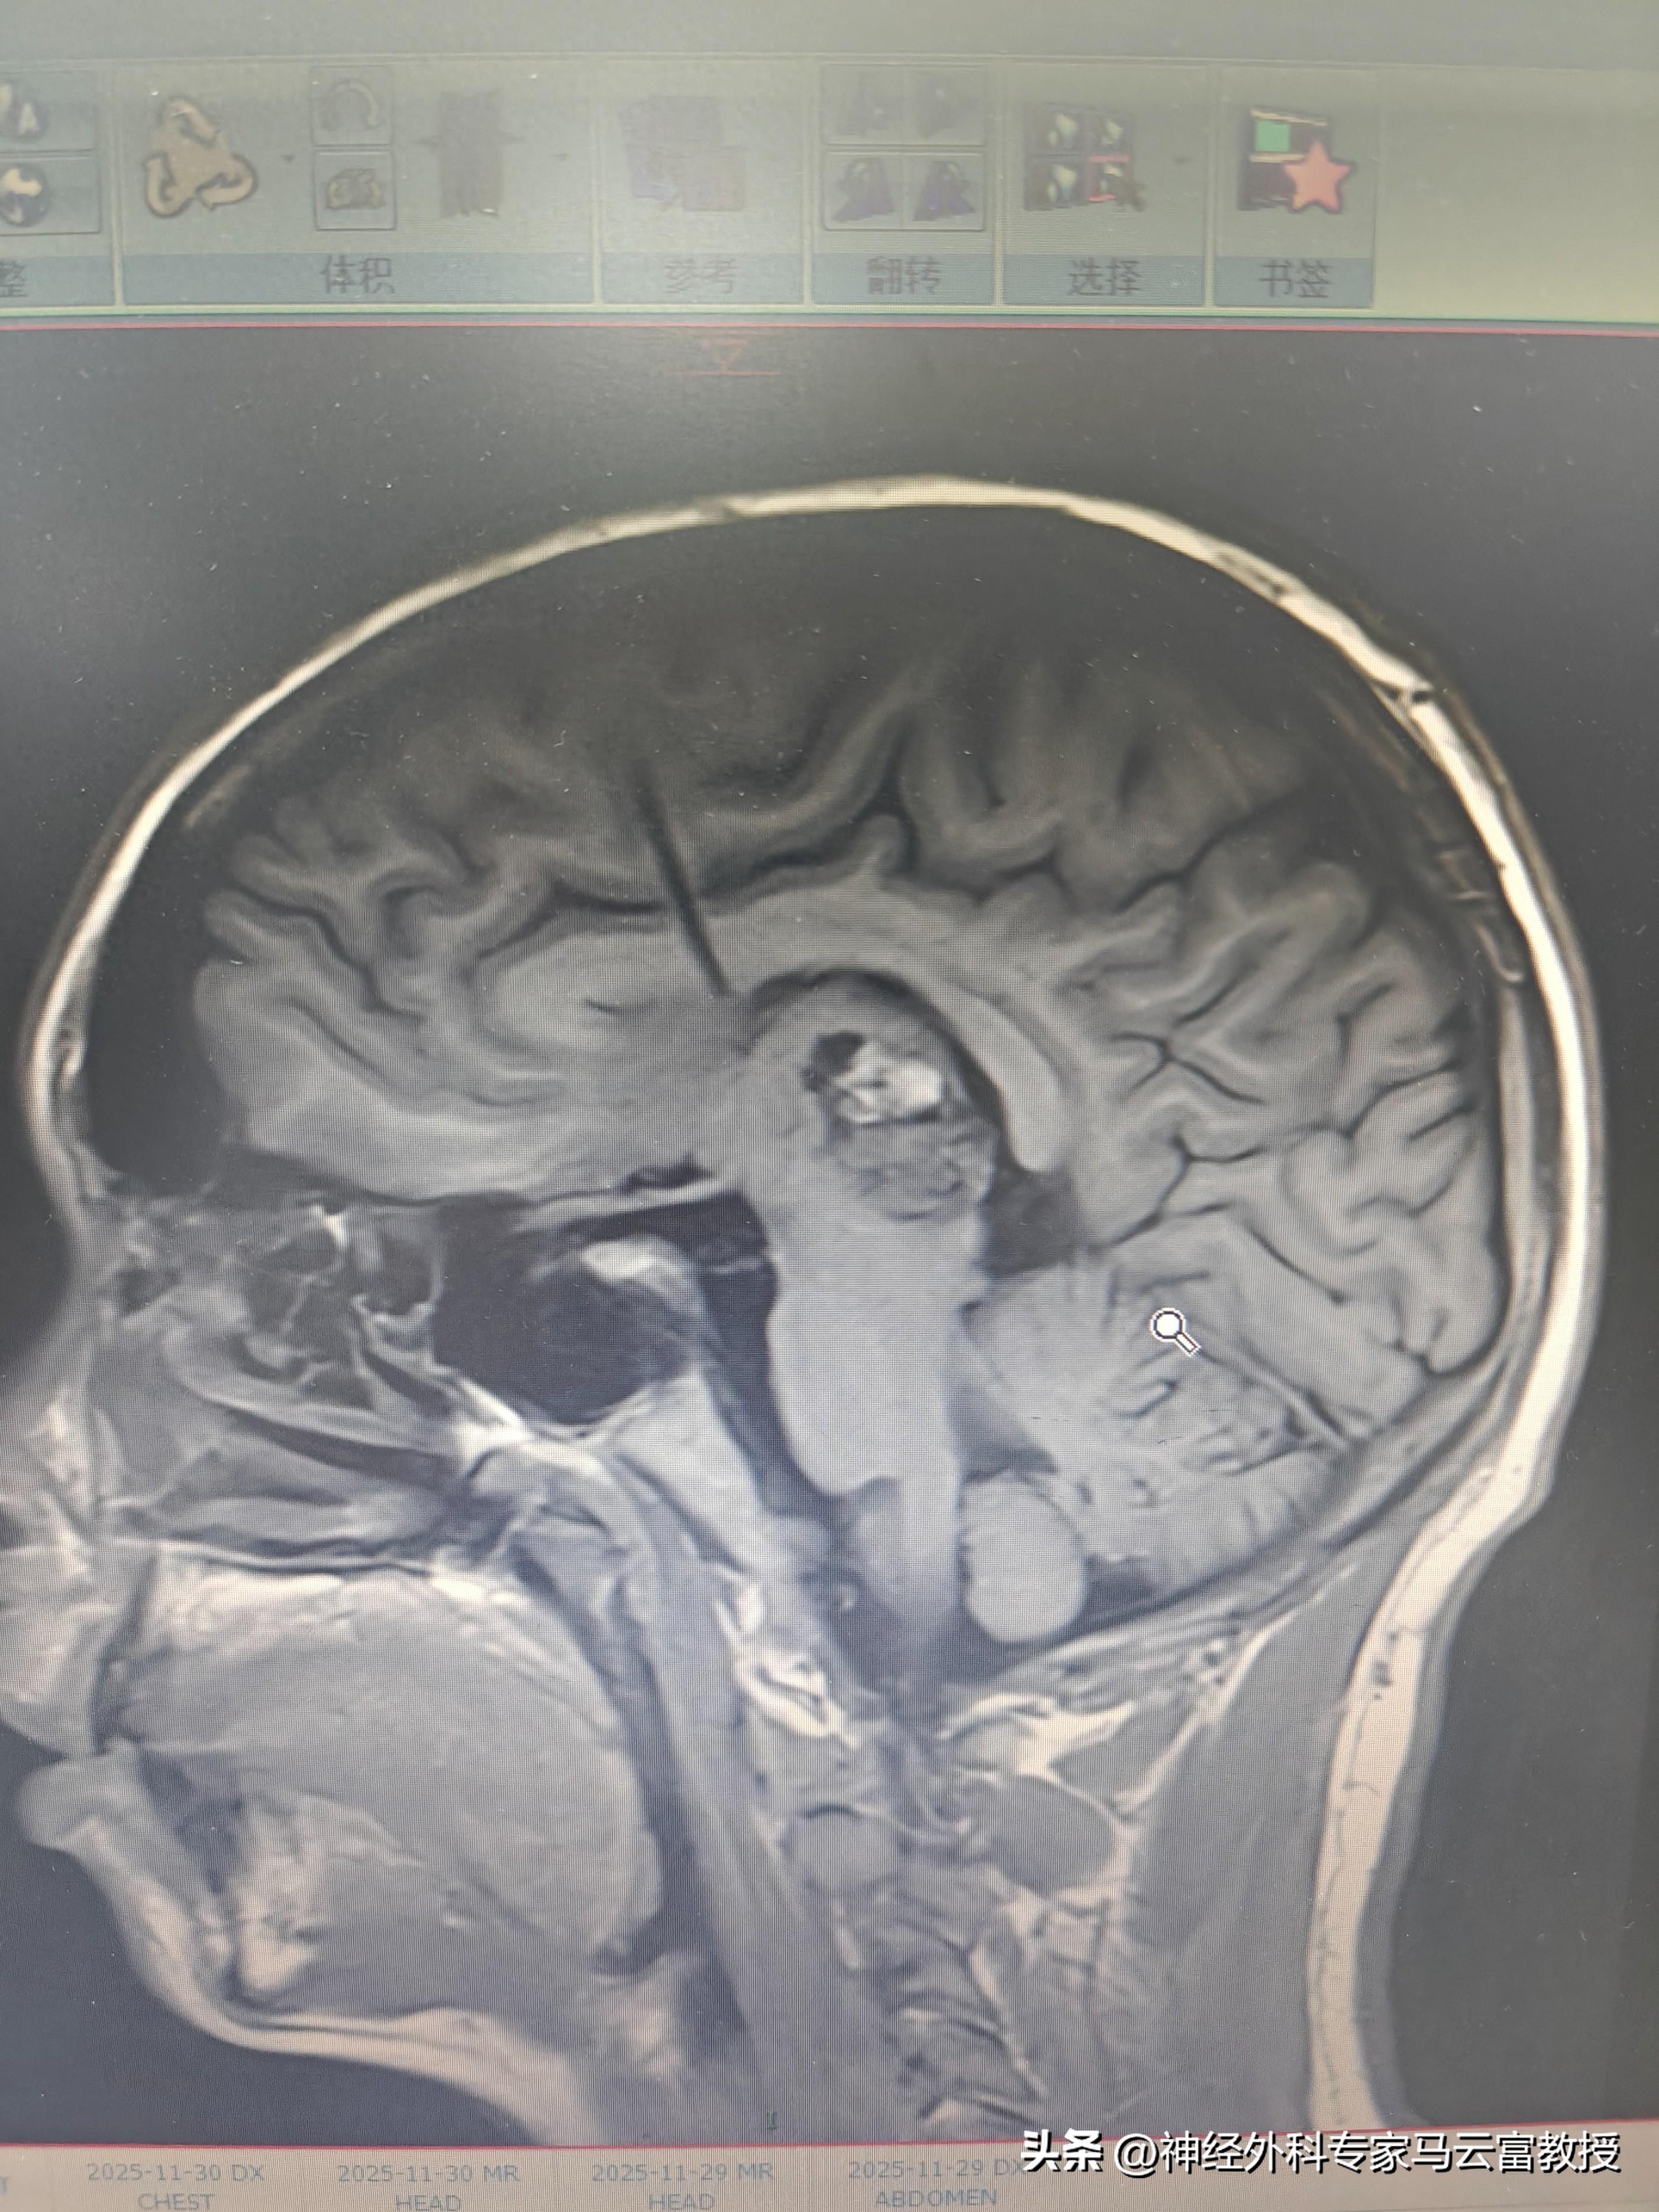

患兒腦腫瘤MRI

但請別絕望,現代醫學賦予了我們明亮的眼睛和精巧的“武器”。核磁共振(MRI) 如同最精密的雷達,能清晰勾勒出腫瘤的“藏身之地”與“真實面目”。而手術,正是這場戰役中最關鍵、最核心的一役——其目標不僅是“切除”,更是“精密地解放”:在毫釐之間,移除病魔,盡全力守護好孩子未來每一個微笑、每一次奔跑、每一份思考的神經基石。